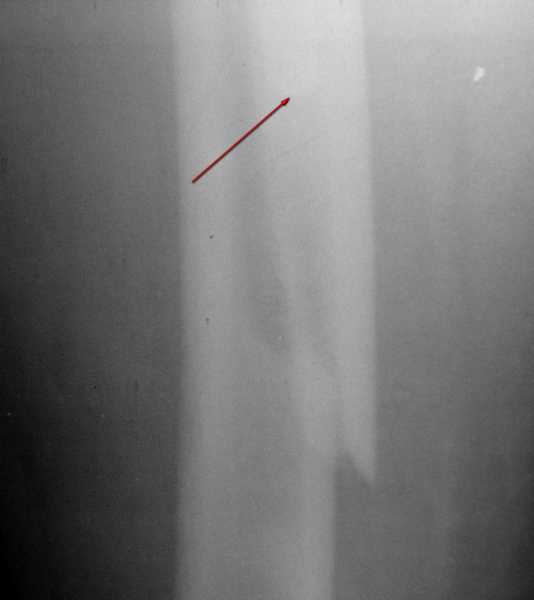

Вот фрагменты этих снимков с более различимыми областями интереса.

Там видно расхождение фрагментов, диастаз чуть медиальнее б. вертела.

Кончик ножки виден на самом верху этого снимка.

1. Спасибо за детализацию. Всё увидел.